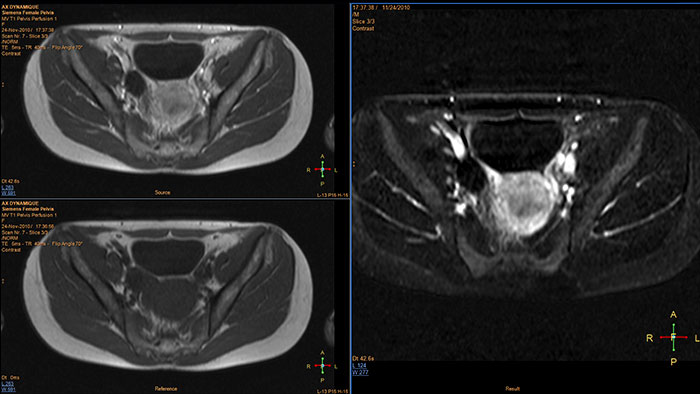

The application generates qualitative and quantitative information about changes in image intensity over time.

Reviewing brain tissue perfusion viability

Provides physicians with supporting information for the evaluation of stroke, or assessment and follow-up of brain tumors. The application supports the analysis of T2* Perfusion studies to generate parametric data including TTP, MTT or Tmax.

Benefits